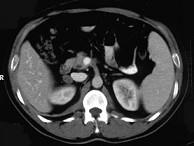

问题 女,23岁,满月脸、向心性肥胖,CT扫描如图所示,应诊断为 ( )

选项 A、右侧肾上腺嗜铬细胞瘤 B、右侧肾上腺转移瘤 C、右侧肾上腺腺瘤 D、右侧肾上腺腺癌 E、右侧肾上腺增生

答案 C